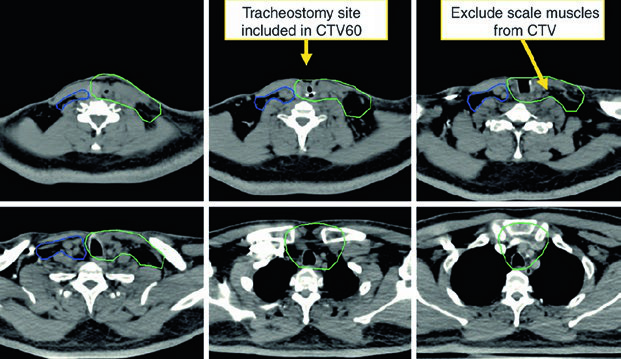

Patients should be simulated supine with a head rest, neck extension, and a five-point custom Aquaplast mask that immobilizes the head, neck, and shoulders. A shoulder pull board can be added when shoulder position interferes with beam entry.

Patients with extensive dental metal may benefit from a custom mouthguard to absorb electron scatter and reduce mucositis. CT simulation should use intravenous contrast, slice thickness of 3 mm or less, and coverage from the vertex through the carina. The isocenter is usually placed at the arytenoids unless there is subglottic or hypopharyngeal extension, in which case it moves 1 cm inferiorly.

In postoperative cases, placing a radiopaque marker over the scar is helpful. For daily image guidance, the preferred approach is daily cone beam CT aligned to the larynx. Daily kilovoltage imaging to bony anatomy plus weekly cone beam CT is also acceptable. Patients should be instructed not to swallow during simulation, IGRT, or treatment delivery.

Postoperative radiation

Postoperative treatment is driven by adverse pathologic features. The chapter lists positive or close margins, extranodal extension, pT4 primary disease, pN2-pN3 nodal disease, perineural invasion, vascular invasion, and lymphatic invasion, citing NCCN v.2020. Concurrent chemotherapy should be added for extracapsular extension or positive margins.

The high-risk postoperative CTV receives 60 Gy and should include the operative bed, scar, stoma, and dissected node-positive neck. Positive margins or extracapsular extension may justify a boost to 66 Gy. The undissected node-negative neck may be included as a low-risk CTV to 54 Gy. If there is subglottic extension or an emergent tracheostomy, the stoma may also be boosted to 66 Gy. The chapter makes the anatomy explicit: a stomal recurrence is a tracheoesophageal node recurrence.